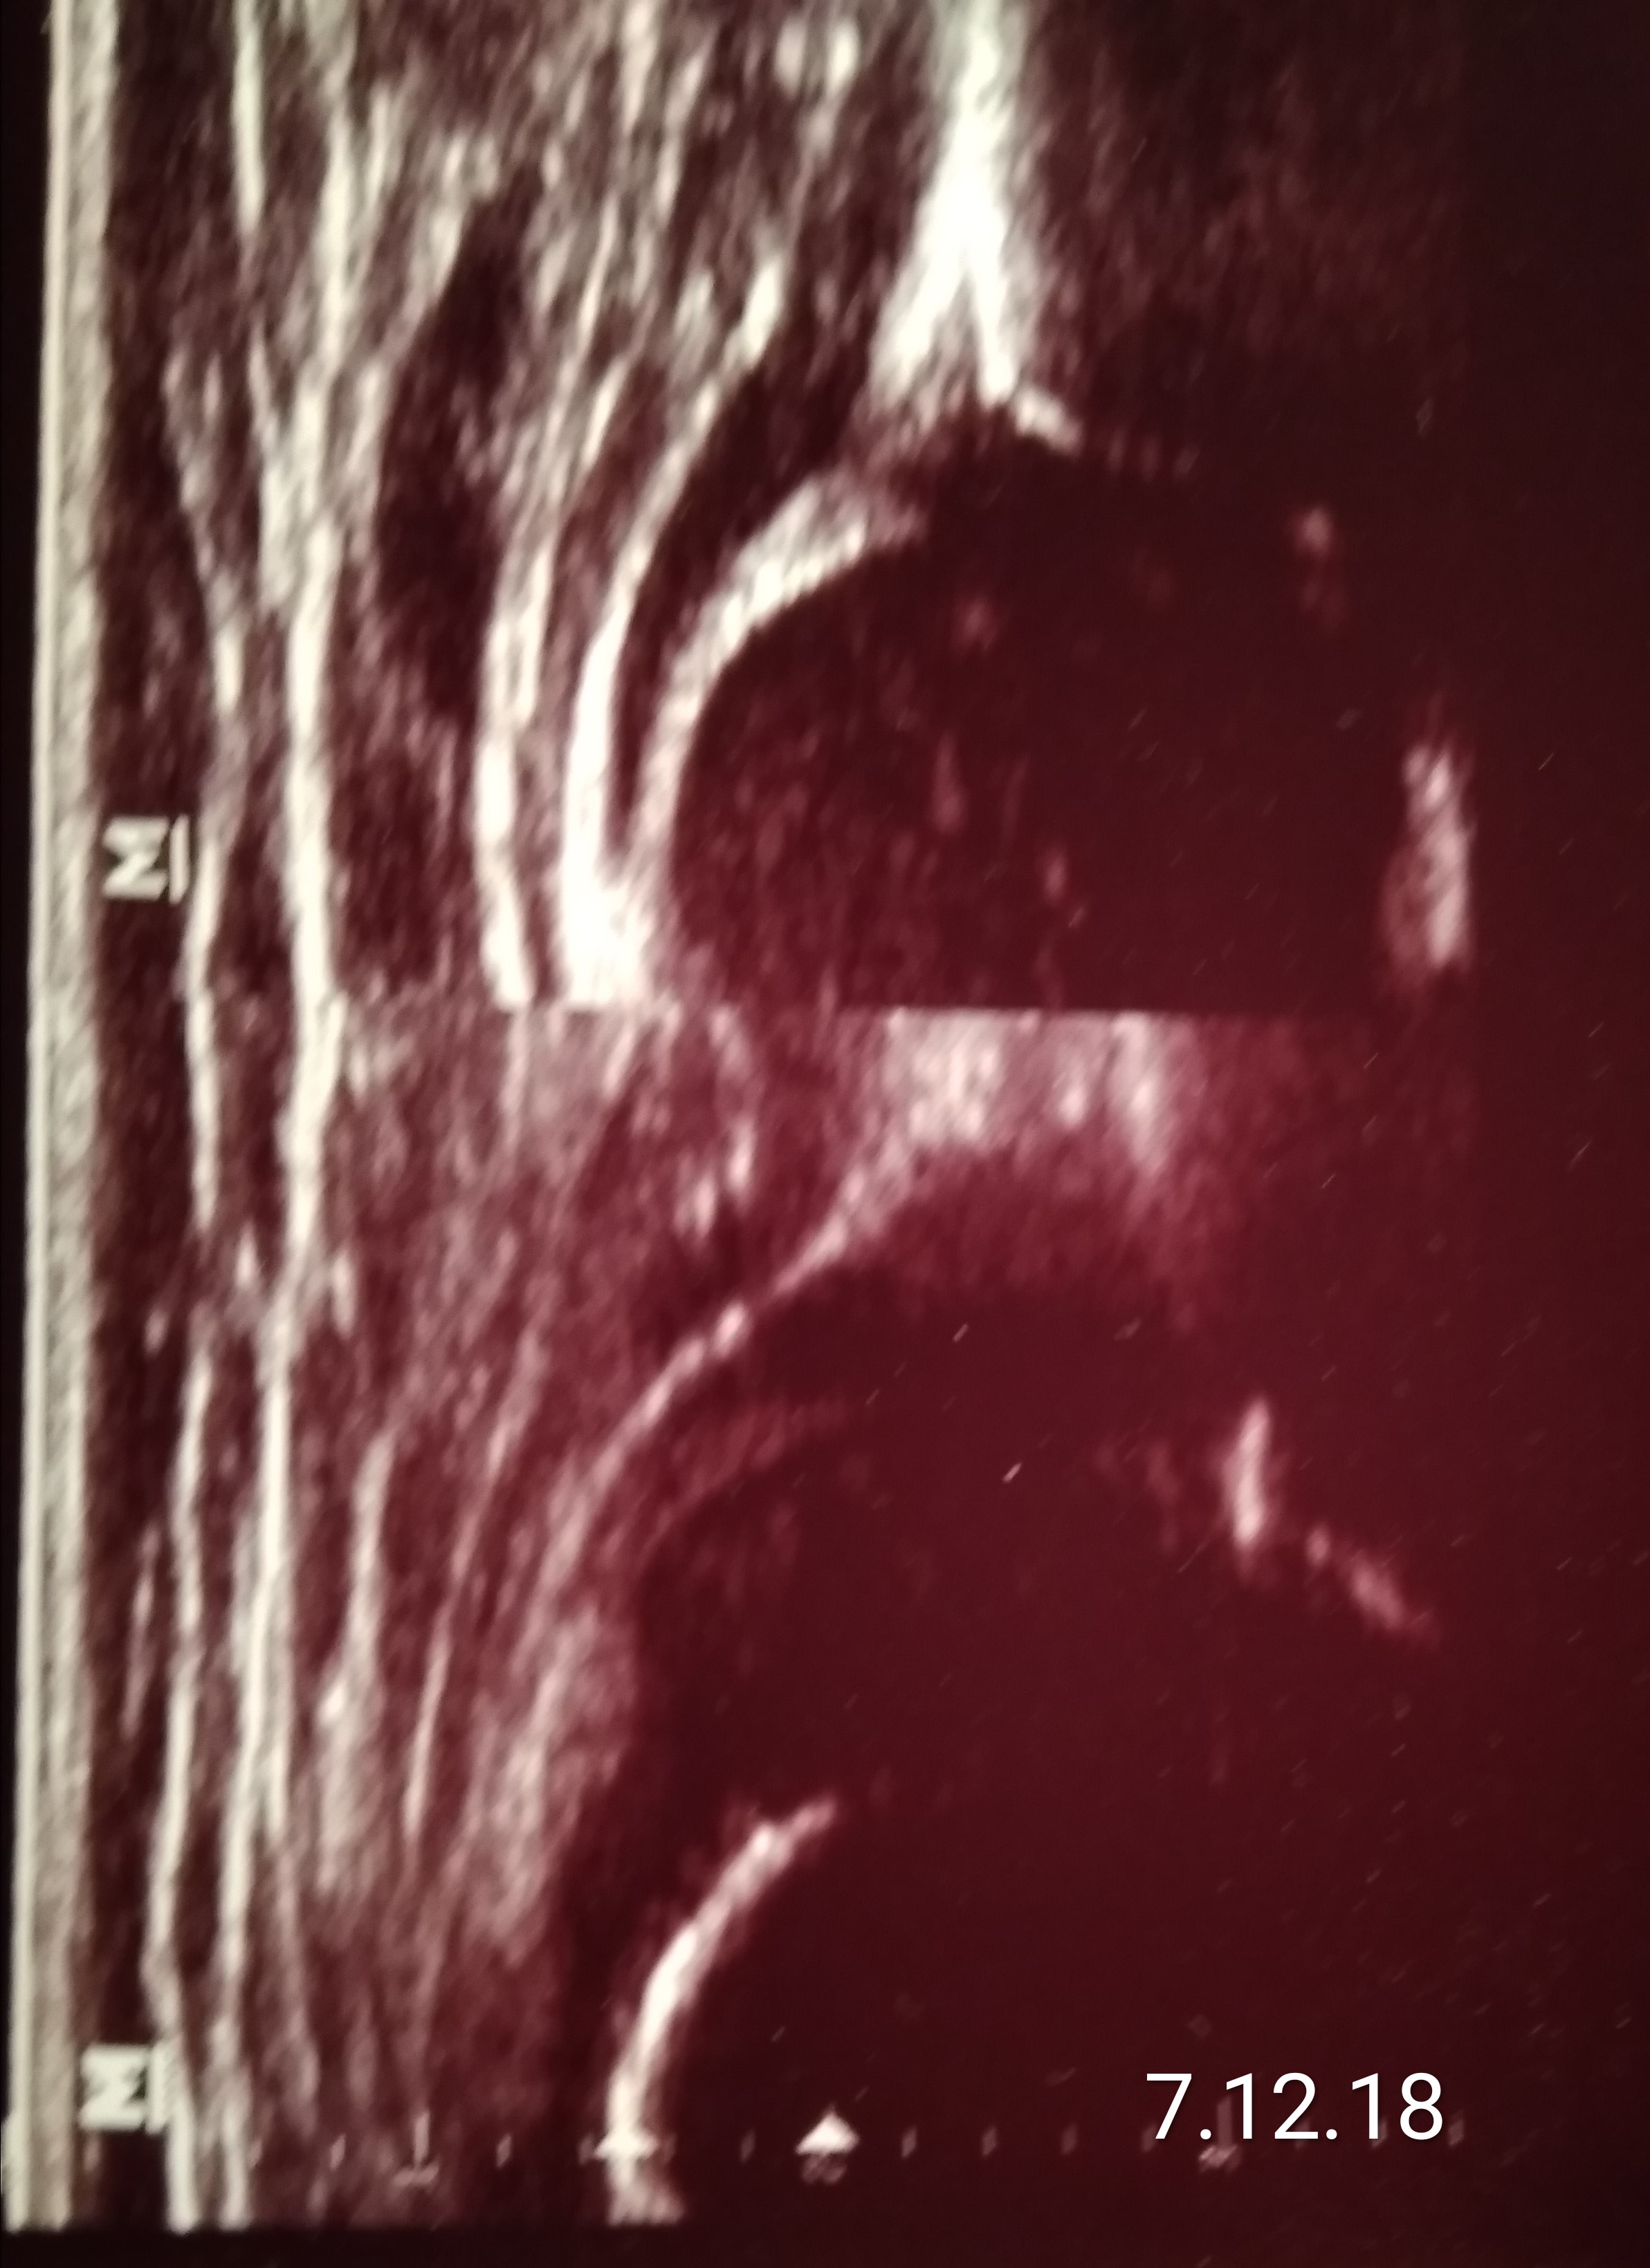

case Natalii

typ IV right hip diagnosis 1month; tratment with orthesis wthout effect for 5 months

rehabilitation was ordered ;

slowy increase from 3 time a week to 3 time a day ( 20 minutes each time)

type IIb but unfortunataly unstable becouse with overgrown lig. capitis fem. (big white echo on the right and below side of the femur's head )